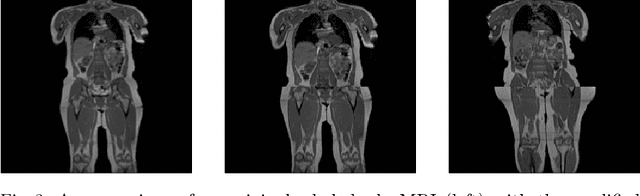

Abstract:Image synthesis is increasingly being adopted in medical image processing, for example for data augmentation or inter-modality image translation. In these critical applications, the generated images must fulfill a high standard of biological correctness. A particular requirement for these images is global consistency, i.e an image being overall coherent and structured so that all parts of the image fit together in a realistic and meaningful way. Yet, established image quality metrics do not explicitly quantify this property of synthetic images. In this work, we introduce two metrics that can measure the global consistency of synthetic images on a per-image basis. To measure the global consistency, we presume that a realistic image exhibits consistent properties, e.g., a person's body fat in a whole-body MRI, throughout the depicted object or scene. Hence, we quantify global consistency by predicting and comparing explicit attributes of images on patches using supervised trained neural networks. Next, we adapt this strategy to an unlabeled setting by measuring the similarity of implicit image features predicted by a self-supervised trained network. Our results demonstrate that predicting explicit attributes of synthetic images on patches can distinguish globally consistent from inconsistent images. Implicit representations of images are less sensitive to assess global consistency but are still serviceable when labeled data is unavailable. Compared to established metrics, such as the FID, our method can explicitly measure global consistency on a per-image basis, enabling a dedicated analysis of the biological plausibility of single synthetic images.